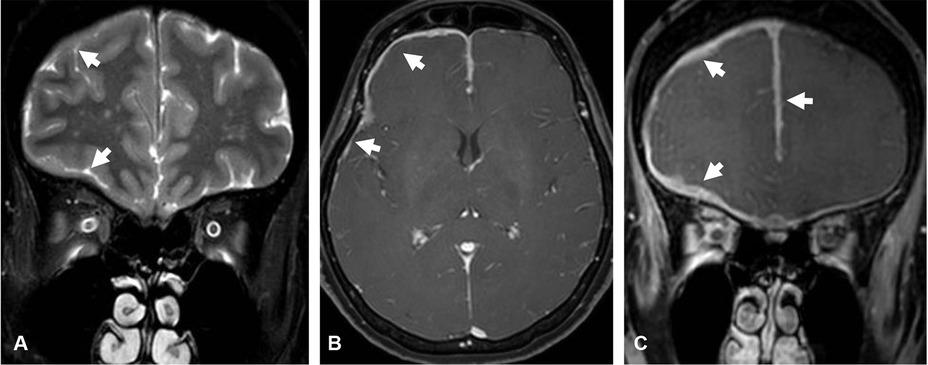

Figure 3